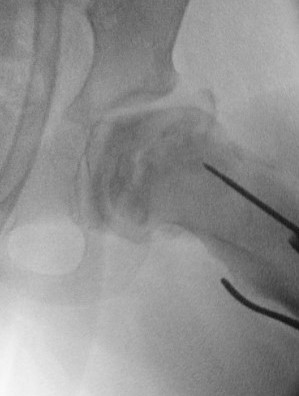

Technique

Patient supine on radiolucent table

- preop antibiotics

- frog leg laterals when needed

Lateral approach

- elevate vas lateralis +/- release proximally with L shaped release

- mark distal and proximal femur with drill holes to check rotation

- place wires up femoral neck short of physis

- use plate to mark osteotomy site

Osteotomy with microsagittal saw 1 cm below lesser tuberosity

- aim for 115o of varus

- avoid excessive varus < 100o to keep greater trochanter distal to femoral neck

- +/- adjust version

- apply plate and fix with screws